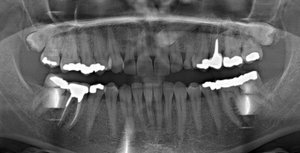

Мне 26 лет, молочные зубы менялись поздно. По личным причинам, когда стал резаться коренной зуб (клык), я не стала вырывать молочный, который был крепким и здоровым. Так на протяжении нескольких лет (очень медленно) прорезался коренной клык и наконец вырос, но на нёбе. Так я ходила с двумя зубками. Никаких неудобств не ощущала. Совсем недавно молочный зуб резко (в течение трёх дней) потемнел.

Помогите, пожалуйста,что нужно делать, удалять оба зуба и ставить мартини? Или после удаления молочного одевать брекеты и ждать пока сдвинется коренной клык?